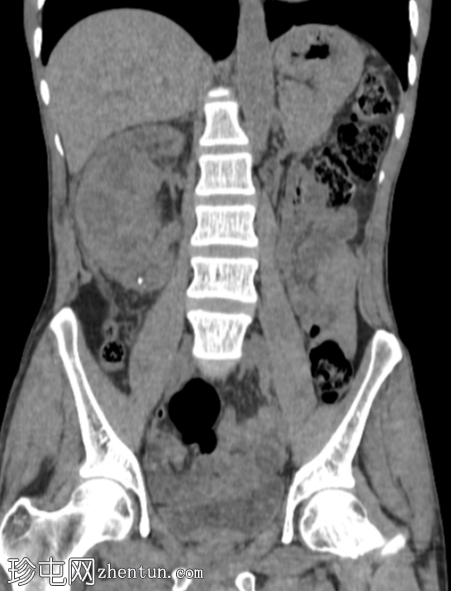

CT

轴位

平扫

右肾前部可见一边界清晰的外生性病变,呈异质性,包含实性及囊性成分,内部可见多发结石。肾周可见模糊影。

左肾体积缩小且萎缩,可见多发结石。

病变内部存在结石及肾周模糊影提示炎症性病变,可能为局灶性黄色肉芽肿性肾盂肾炎(XGP),而非肿瘤性肿块(肾细胞癌)。